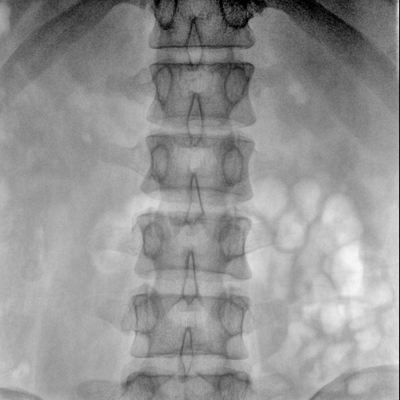

Clinical picture

临床图片

骨科: 经皮锥体成形术、经皮椎间盘臭氧治疗术、胸脊椎固定、骨活检、腰椎内固定术等。